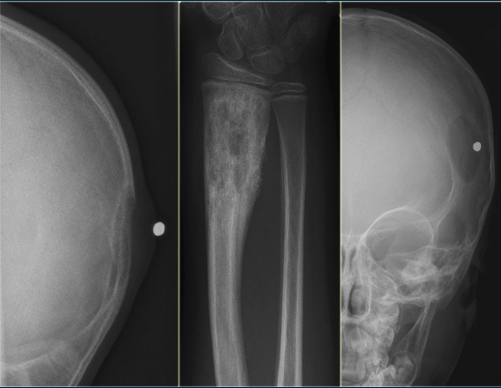

Q

Eosinophilic Granuloma

There are 3 classic appearances - for the purpose of multiple choice:

A

(1) Vertebra plana in a kid

(2) Skull with lucent “beveled edge” lesions (also in a kid).

(3) “Floating Tooth” with lytic lesion in alveolar ridge — this would be a differential case

The appearance is highly variable and can be lytic or blastic, with or without a sclerotic border, and with or without a periosteal response. Can even have an osseous sequestrum.

As such, EG can be very similar in appearance to a Brodie abscess / subacute osteomyelitis (similar imaging, similar ages - peds).